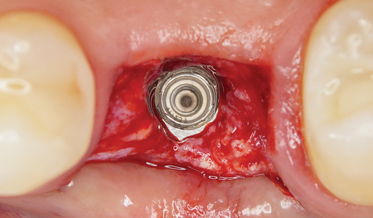

Advances in Esthetic, Immediate Tooth Replacement Therapy Aimed at Improving Clinical Outcomes

Barry P. Levin, DMD